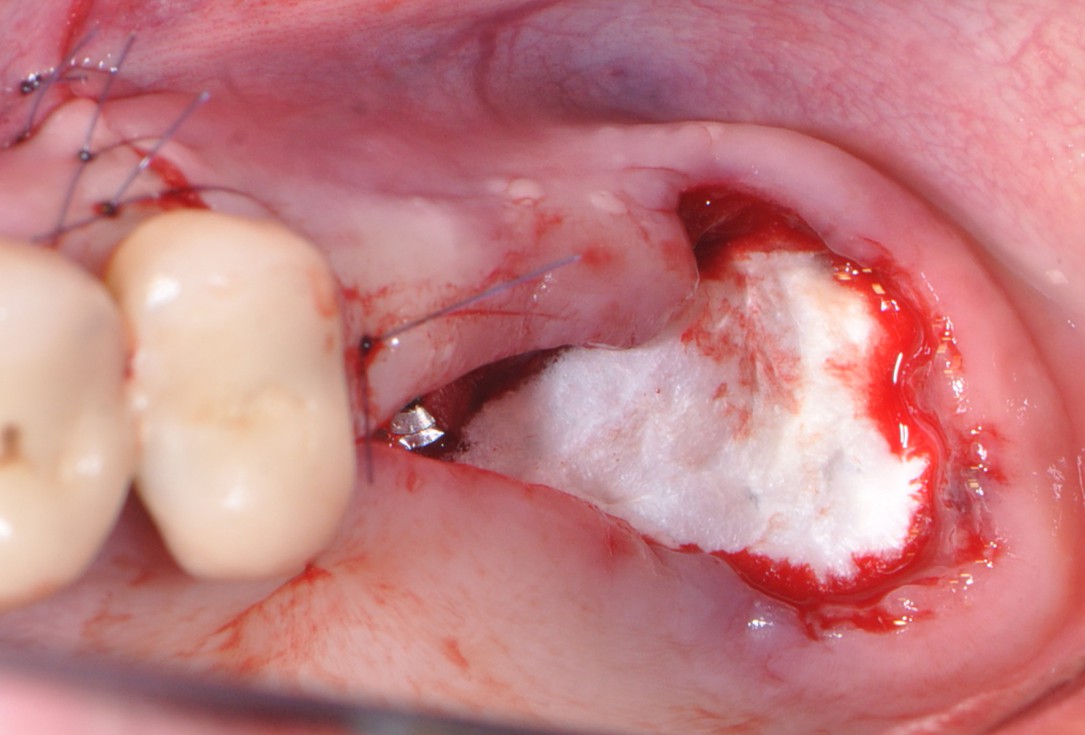

10/16 - Soft tissue defect coverage with collagen fleece

One-stage sinus lift - Dr. V. Kalenchuk

11/16 - Wound closure and suturing

One-stage sinus lift - Dr. V. Kalenchuk